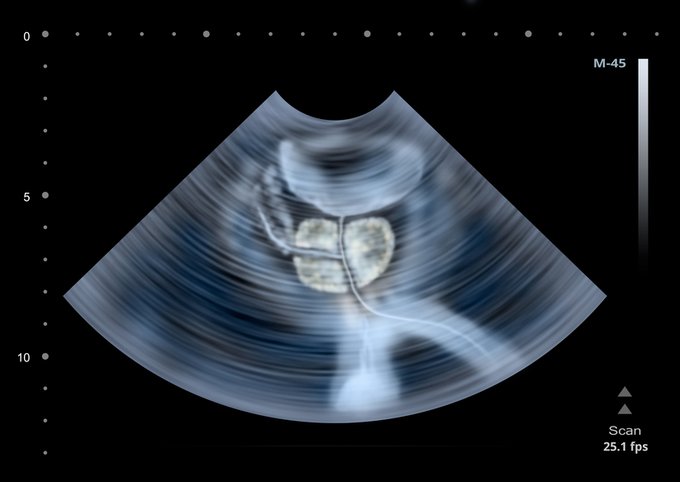

A medida que los hombres envejecen, la próstata se va agrandando. Si se agranda demasiado, puede causar problemas. Aquí lo que debes saber sobre el agrandamiento de la próstata ow.ly/BSmf50ASloq #BuenJueves